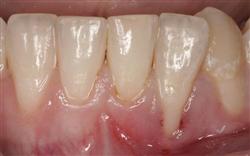

Cosmetic Soft Tissue Grafting

In addition to the functional problems previously mentioned, receding gums can look unsightly.

Longer looking teeth and exposed tooth roots give an "old" appearance to your smile. Some people cover their mouths when they smile for this very reason.